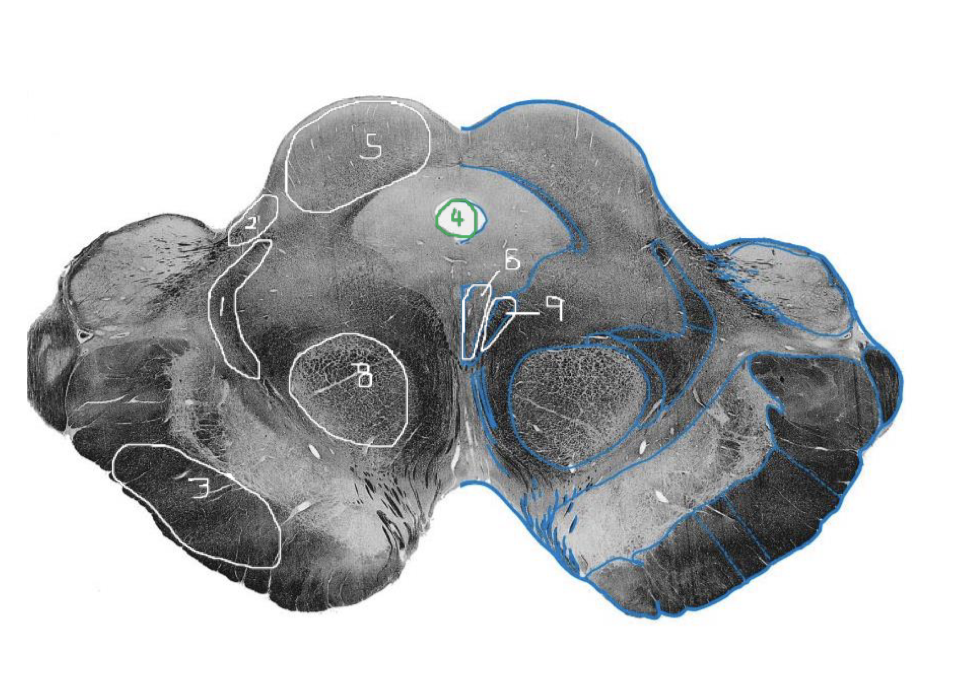

1

Medial Lemniscus - Caudal Midbrain

2

Spinothalamic Tract - Caudal Midbrain

3

CST - Caudal Midbrain

4

Cerebral Aqueduct - Caudal Midbrain

5

Superior Cerebellar Peduncle (Decussation) - Caudal Midbrain

6

Inferior Colliculus - Caudal Midbrain

7

Trochlear Nucleus (CN IV) - Caudal Midbrain

8

Medial Longitudinal Fasciculus (MLF) - Caudal Midbrain